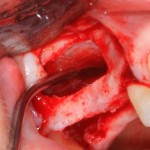

Рисунок 43, 44, 45. Установка имплантов одномоментно с операцией синуслифтинга: слева – этап синуслифтинга, в центре – подготовка лунки под имплантат (виден спейсер и слизистая оболочка гайморовой пазухи), справа – установленный имплант

При наличии соответствующих условий возможно проведение операции немедленной имплантации одновременно с синуслифтингом (рис 54, 55, 56):